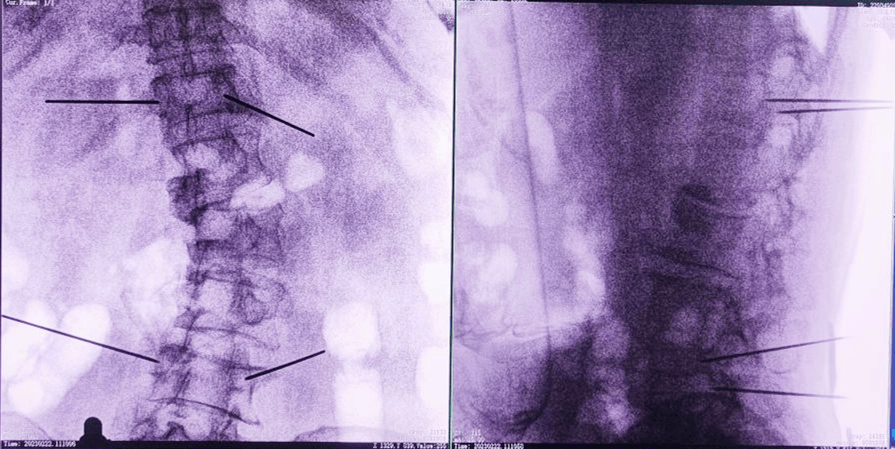

經(jīng)皮椎體成形術(shù),也就是俗稱的“骨水泥手術(shù)”。骨水泥是一種高分子材料,在凝固以前,骨水泥是膠狀的;凝固之后則硬的像骨頭一樣。治療的時候,醫(yī)生首先要在X光的引導(dǎo)下找到病人骨折的脊椎,之后把一根毛衣針粗細的中空穿刺針,通過皮膚穿刺到受損的椎體內(nèi)。

王伯堯主任說道,在常規(guī)的骨科手術(shù)中,盡管醫(yī)生們有著豐富的經(jīng)驗和精湛的技術(shù),但在面對復(fù)雜的手術(shù)時,仍然會存在一定的誤差和風(fēng)險,往往還需要借助X光射線在術(shù)中透視看到骨頭,為了定位準(zhǔn)確,患者要反復(fù)“吃”射線。一次定位不準(zhǔn)還要重新透視再次打螺釘進行調(diào)整。而骨科手術(shù)機器人輔助手術(shù)的意義,就是為了減少人手置釘產(chǎn)生的誤差,通過準(zhǔn)確的定位系統(tǒng)將螺釘準(zhǔn)確地置入到理想的位置,一步到位。

術(shù)中,手術(shù)團隊先對患者進行三維影像掃描,將圖像同步傳輸至機器人成像系統(tǒng)后,利用骨科手術(shù)機器人導(dǎo)航系統(tǒng)做好手術(shù)規(guī)劃,隨后利用其機械臂,將手術(shù)工具精確定位到“目的地”,鋪好“通道”,這就很好的解決了醫(yī)生“盲穿”的問題。